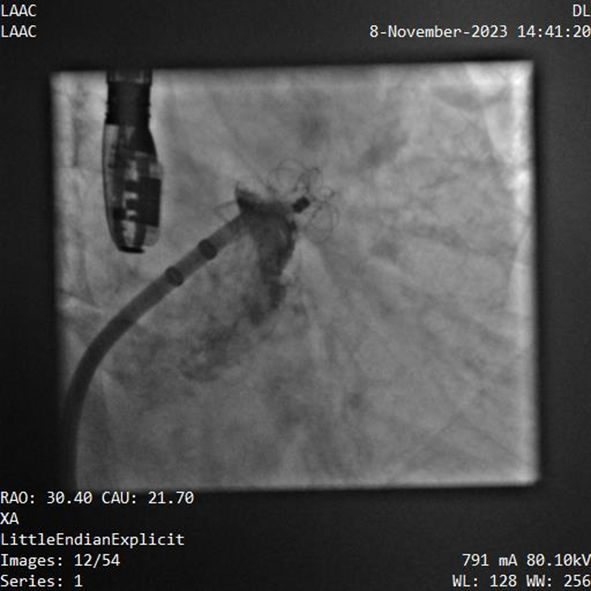

該例患者為男性58歲,陣發(fā)性房顫,9個月前突發(fā)急性腦梗死,3月前曾行房顫射頻消融術。2023年11月經(jīng)胸超聲心動圖示左房內(nèi)徑46mm,經(jīng)食道超聲心動圖示左心房及左心耳內(nèi)未見血栓形成,CHA2DS2-VASc評分3分,HAS-BLED評分2分。DSA測得左心耳開口直徑約23mm,錨定區(qū)域約18mm。

葛均波院士、周達新教授等經(jīng)詳細評估和討論后,認為該受試者需要植入固定部20mm、封堵盤28mm的左心耳封堵器,為非常規(guī)固配規(guī)格,SimuLock的可選配組裝式設計精準滿足患者需求。

手術過程順利,通過植入非常規(guī)固配規(guī)格的固定部20mm、封堵盤28mm的左心耳封堵器,實現(xiàn)左心耳完全封堵,達到手術預期效果,再次體現(xiàn)產(chǎn)品獨特的設計創(chuàng)新優(yōu)勢。

器械釋放后造影示封堵器展開良好,封堵完全